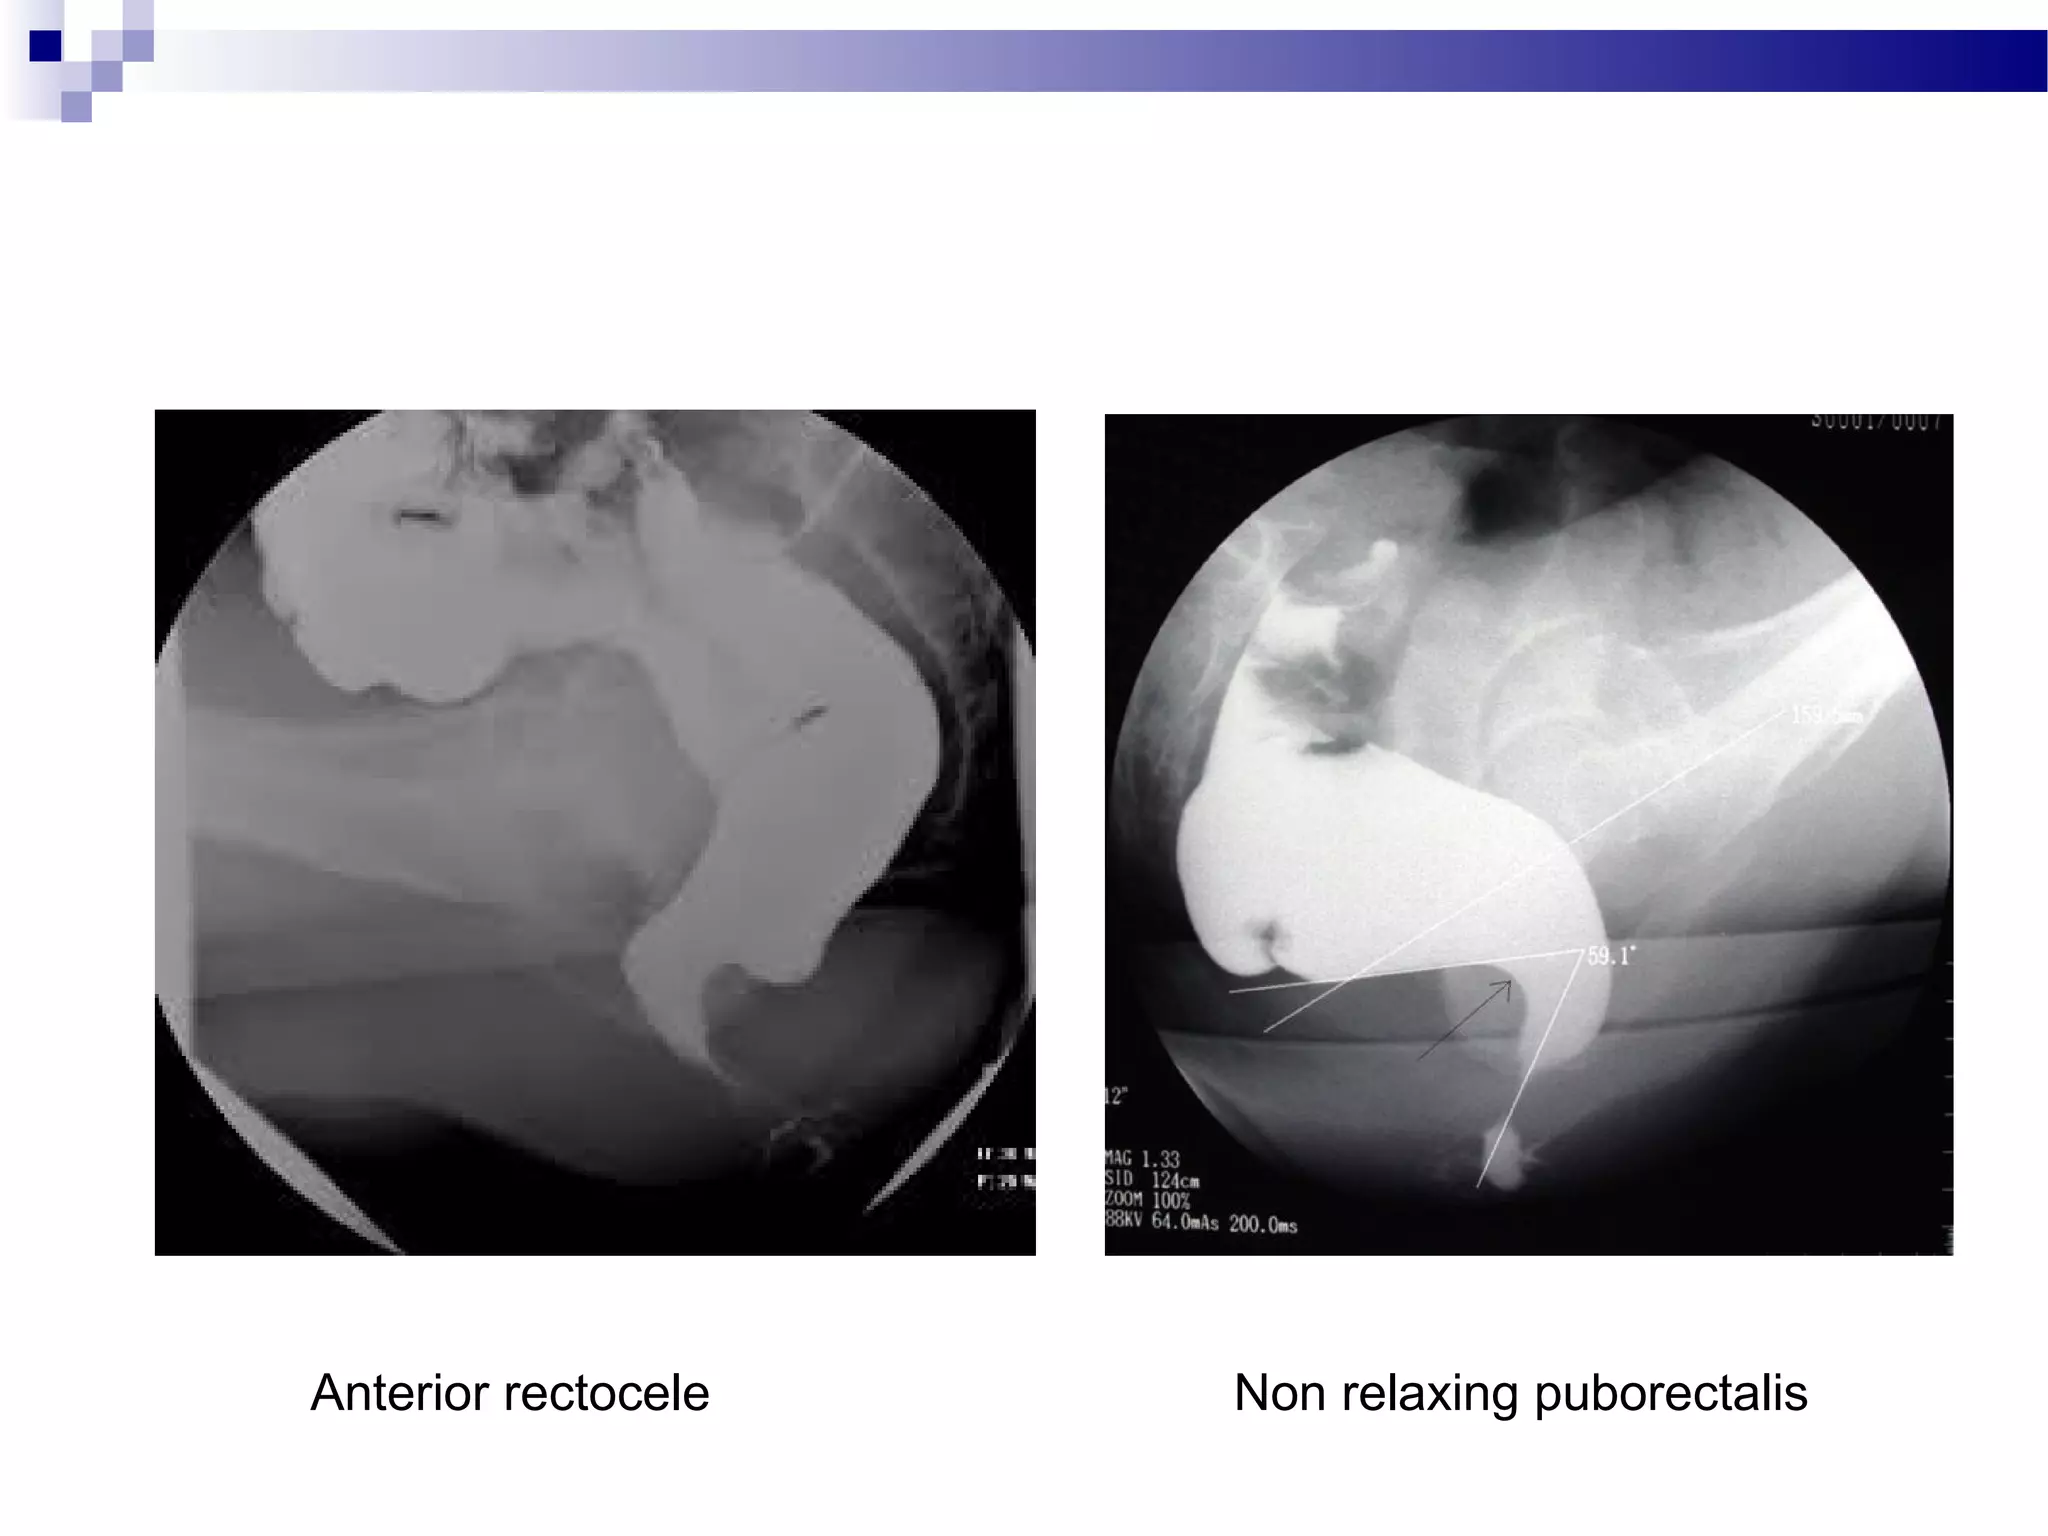

Constipation Due to Pelvic Floor Disorder

Anterior rectocele Non relaxing puborectalis